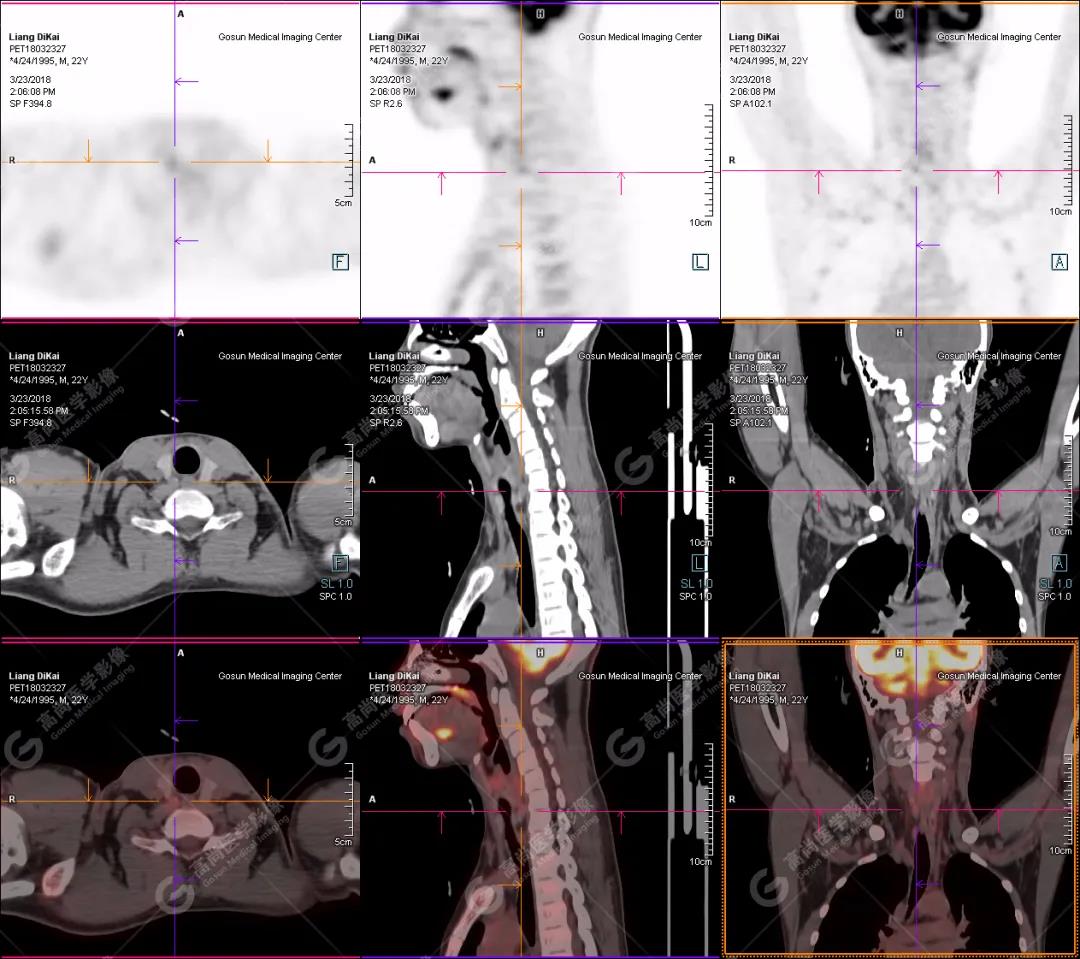

本中心PET/CT提示

1.右肘關(guān)節(jié)周圍、骶尾部皮下、雙側(cè)臀部、盆腔左側(cè)壁及左側(cè)大腿根部肌肉、肌間隙多發(fā)結(jié)節(jié)狀、片塊狀及不規(guī)則巨塊狀高密度鈣化灶,伴代謝不均勻輕度增高,考慮為鈣質(zhì)沉著癥;

2.甲狀腺雙葉后方多發(fā)(右2個,左1個)小結(jié)節(jié)狀軟組織影,部分代謝輕度增高,多考慮為甲狀旁腺腺瘤。